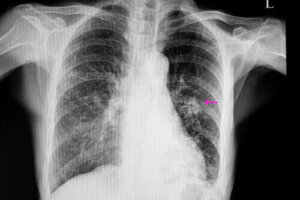

Tällaisissa tapauksissa paiseella on epäsäännöllinen ulkonäkö ja rosoiset tai epäsäännölliset reunat; tämä voidaan havaita röntgenkuvissa. Pahanlaatuiset keuhkopaiseet ovat yleensä pienempiä kuin hyvänlaatuiset. Niihin liittyy joitakin riskitekijöitä, joista tavallisimpia ovat:

Kun nämä alkurutiinit on saatu tehtyä, lääkärin on suoritettava tarvittavat kuvantamiskokeet paiseen löytämiseksi. Kuvien avulla voidaan tarkkailla myös paiseen ominaisuuksia, kuten muotoa ja kokoa. Tämä on tärkeää siksi, että sen ominaisuuksien kautta voidaan määrittää onko paise mahdollisesti pahanlaatuinen vai onko se hyvänlaatuinen.

Yleisimmät kuvantamiskokeet keuhkopaiseen diagnosoimiseksi ovat röntgenkuvat rintakehästä sekä tietokonetomografia (TT-kuvaus). Keuhkopaiseen tarkan syyn selvittämiseksi lääkäri voi joskus joutua ottamaan koepalan, sillä sen avulla voidaan analysoida itse kudosta.